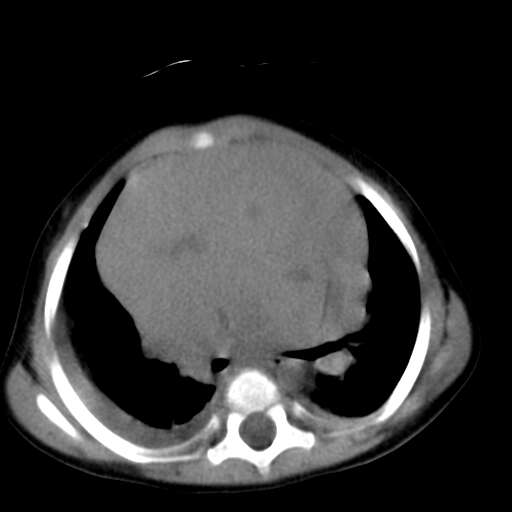

患儿1y,女,因支肺炎经dr检查发现前上纵膈占位而行ct检查,肿块与心血管脂肪间隙模糊消失,可见斑点状钙化,未见脂肪成分,双侧胸水,考虑侵袭性胸腺瘤

1、定位:前上纵隔,血管及头臂干前方,胸腺部位。

2、巨大实性肿块,其内见小片状低密度灶和少许点状钙化。

3、双侧胸腔积液,提示肿瘤恶性可能。

4、双肺下也背侧肺间质水肿改变。